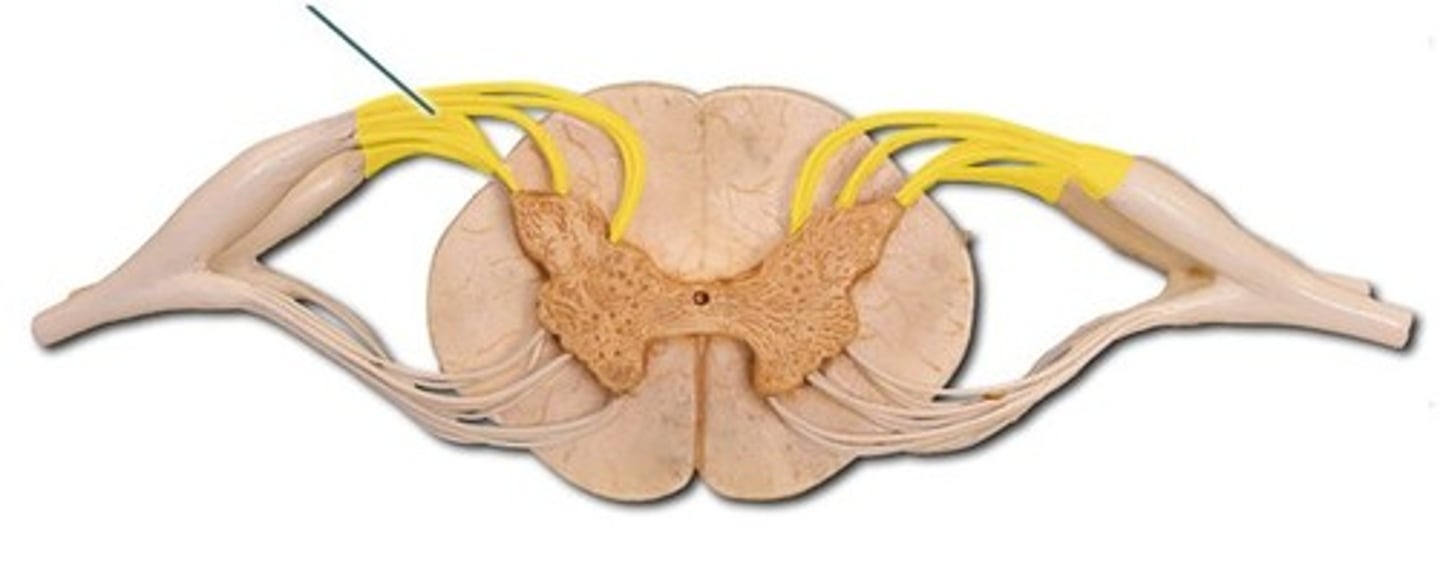

anterior (ventral) root (of spinal cord)

dorsal root ganglion (spinal)

posterior (dorsal) root (of spinal cord)

spinal nerve